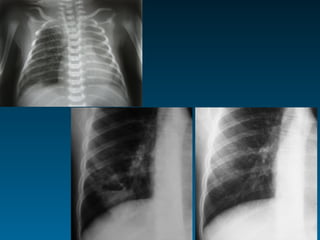

Τεχνικοί παράγοντες: στροφή

Τεχνικοί παράγοντες: όγκος πνευμόνων

ό   Ποσοστό καρδιάς κάτω από ημιδιάφραγμα στην face α/α

ό   Κυρτότητα-επιπέδωση ημιδιαφραγμάτων

ό   Πρόσθια άκρα των πλευρών και ημιδιάφραγμα

3η-4η: εκπνοή       5η-6η: εισπνοή > 7η:παγίδευση αέρα